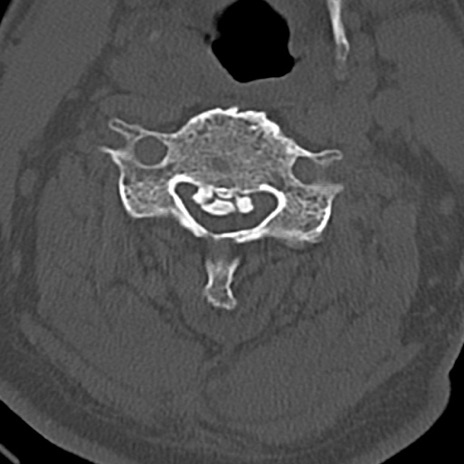

頚椎CT

横断像